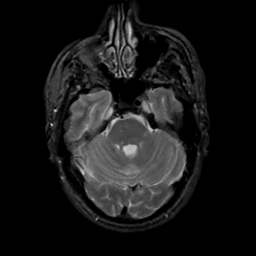

MR Study #2, February 17, 1991 -- Slice #14

[Home][Help][Clinical][Tour 1][Tour 2] Slice 14